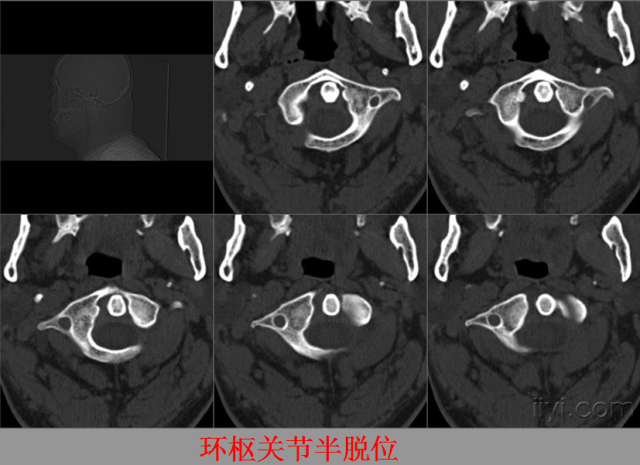

关节脱位篇

02

定义:关节脱位是暴力、关节感染、附近软组织挛缩或先天骨发育障碍造成的关节对位关系部分或完全脱离,即为半脱位或脱位。临床上以创伤性脱位*常见。